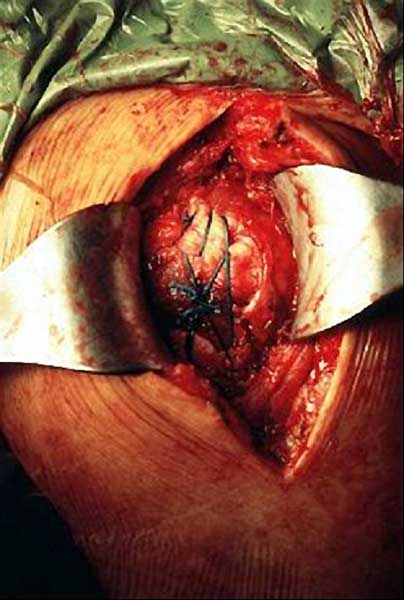

在术中发现肩袖缺损时,如果在肩关节中立位肩袖组织足够在正常张力下缝合就将其修补固定在骨上。达不到要求时强行修补可能效果不佳。在进行了肩袖修复或大小结节固定的情况下,术后康复训练必须完全改变,使肩袖组织能够在主动活动前达到确实的愈合。根据以上原因,在肩袖缺损时通常不进行修补,这些病例通常考虑进行半关节置换,而不是全肩关节置换。